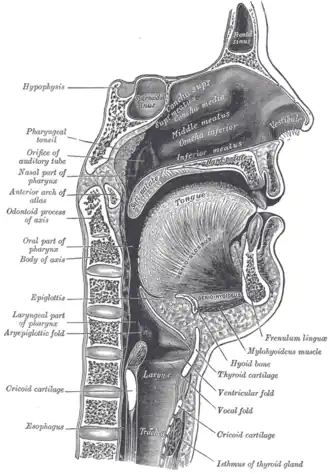

The nasopharynx, oropharynx, and laryngopharynx or larynx can be seen clearly in this sagittal section of the head and neck.

The nasopharynx, oropharynx, and laryngopharynx or larynx can be seen clearly in this sagittal section of the head and neck.